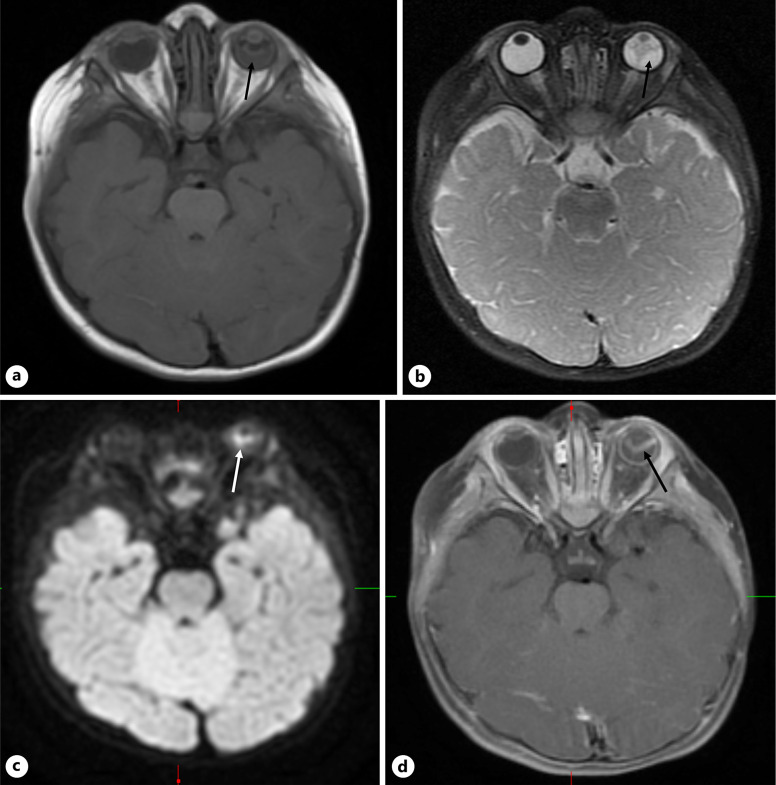

Case presentation: An 11-month-old female presented with poor visual behavior since birth and an intraocular mass in the left eye. Examination under anesthesia revealed a detached retina rolled into a stalk attached to the optic nerve in the right eye and a white retrolental mass with perfused vessels in the left eye. Magnetic resonance imaging demonstrated a heterogeneous mass filling the left globe with diffusion restriction and contract enhancement. Aqueous humor liquid biopsy was performed in both eyes with low DNA yield and no mutations associated with retinoblastoma were identified. The patient was observed with no interval change in examination for 6 months.